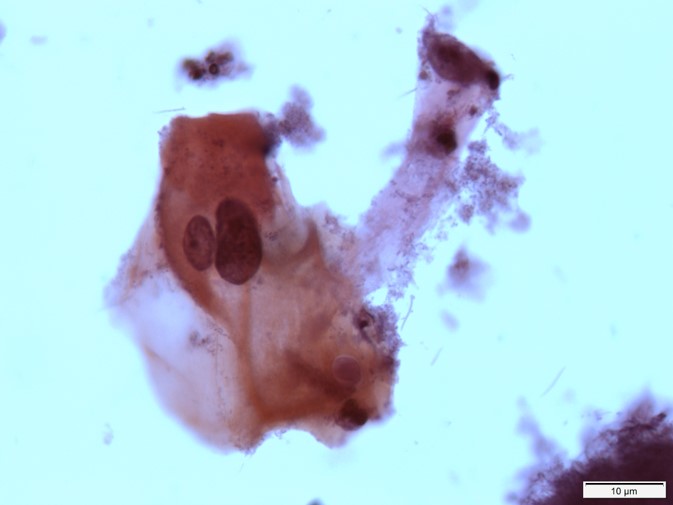

Células Parabasais

Estas células tendem a ter aspecto mais arredondado com núcleo abundante esférico central e citoplasma basofílico escasso. A relação núcleo citoplasma nessas células é maior. A membrana nuclear é suave e regular e a cromatina é pouco corada e delicada.

Quais estruturas estão identificadas pelas setas preta, vermelha e azul?

Quais estruturas estão identificadas pelas setas preta, vermelha e e pelo circulo preto?

Quais estruturas estão identificadas pelas setas pretas?

Podemos incluir as células que estão dentro do círculo preto na análise? Por que?

Podemos incluir as células que estão nesta imagem na análise? Por que?